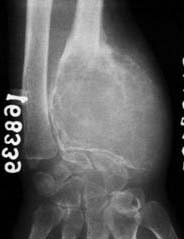

临床与病理:1、年龄:20-40岁,约65%;2、部位:长管状骨骨端,膝关节附近居多

X线表现:① 多数为偏心性骨破坏 (溶骨型)② 局部骨 膨胀性,骨皮质变薄形成薄层骨壳,无硬化边③ 大小不一的分隔小房呈肥皂泡状, 并见骨嵴。

④ 无骨膜反应,⑤一般不穿破关节软骨

桡骨远端偏侧性膨胀性骨质破坏,中有骨嵴。